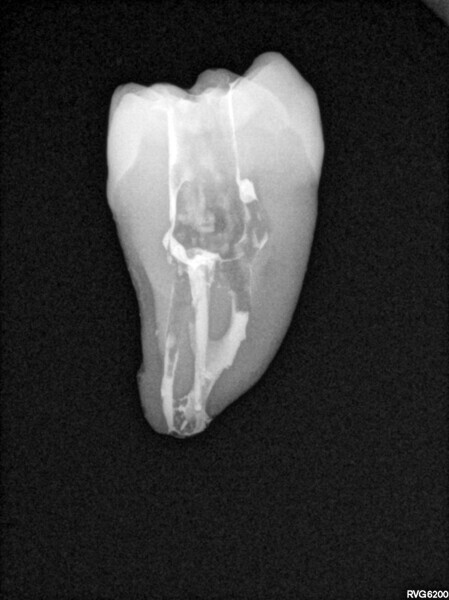

The first trials of the LPE concept were performed on extracted human molars. Although the dynamics of fluid during root canal irrigation are completely different in vivo than in extracted teeth, these kinds of trials provide initial information about the procedure. Some of these teeth had apices closed with a coat of wax and composite resin to close the apical delta and simulate the periapical tissue. After creation of the access cavity, the pulp chamber was cleaned with continuous irrigation with 5.25% NaClO activated with a SkyPulse laser (Fotona) in AutoSWEEPS mode (20 Hz, 15 mJ). A 25/0.07 reciprocating file (Shenzhen Perfect Medical Instruments) was used to perform the pre-flaring procedure. After opening the coronal third, continuous irrigation with 5.25% NaClO activated with the laser was used to clear the debris for 30 seconds. After removing the debris, a #10 C-PILOT file (VDW) was used to establish apical patency, without forcing the file if possible. In some cases, apical patency was reached already at this stage of root canal preparation. In all cases, the second step of instrumentation was the preparation of the middle third with the same file, and the same irrigation procedure was performed. Subsequently, the C-PILOT file was used to reach the apical foramen. At this stage, apical patency was reached in most cases, but in some roots, there was no possibility of entering the apical foramen. The working length was confirmed with a radiograph with the hand file. Usually, the next procedure to be done is apical preparation, but the LPE concept is based on an enhanced irrigation protocol. Following this protocol, irrigation was performed for 5 minutes with continuous flow of 5.25% NaClO activated with the SkyPulse laser in AutoSWEEPS mode (20 Hz, 20 mJ) with a conical sapphire fibre. The next step was alternating irrigation with 17% EDTA for 30 seconds, with 5.25% NaClO for 30 seconds and with 17% EDTA for 30 seconds, all activated with AutoSWEEPS, followed by irrigation for another 5 minutes with 5.25% NaClO activated with AutoSWEEPS. In most cases, the next step after this stage of enhanced irrigation was the calibration of the apical constriction rather than apical preparation per se, but this step requires further investigation.

During the in vitro stage, different protocols for shaping the apical third were used. In some cases, only the coronal and middle thirds of the roots were prepared; in some cases, apical preparation was performed only with a #15 K-file; and in some cases, the preparation was performed with a 25/0.07 reciprocating file. No significant difference was observed in terms of the apical extrusion of the sealer and the homogeneity of the sealing material, but the sample size was too small to determine definitively whether the LPE enhanced irrigation protocol could replace the apical preparation stage.